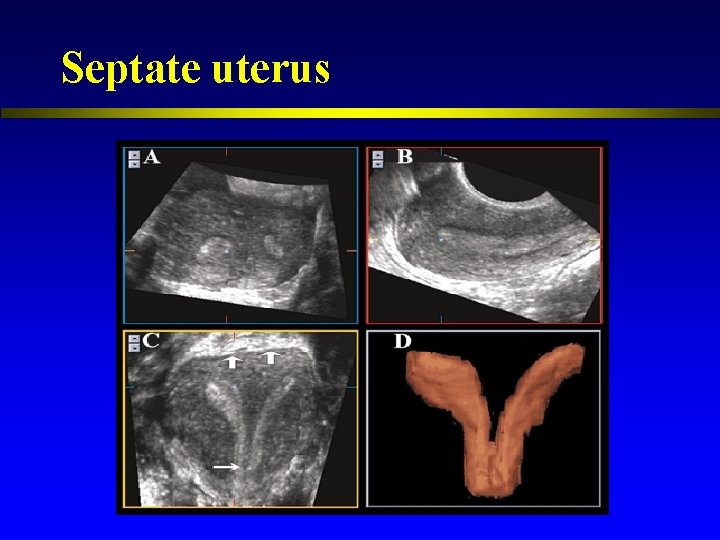

Septate uterus

Congenital uterine anomalies l l l Associated with a range of adverse reproductive outcomes Septate uterus had a higher proportion of 1 st trimester loss compared with women with a normal uterus. Women with an arcuate uterus had a greater proportion of 2 nd trimester loss and preterm labor. (Woelfer et al. , 2001)